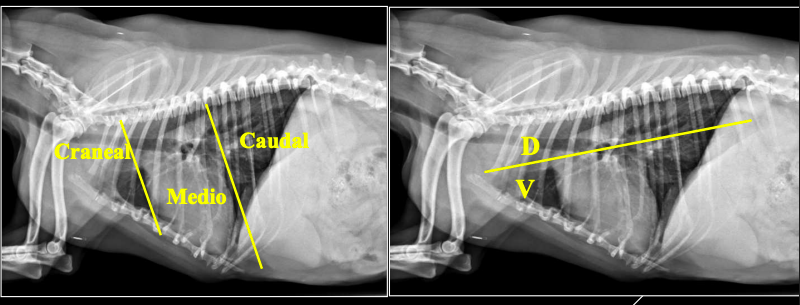

- Número de radiografías: como mínimo dos perpendiculares.

- Proyecciones: LL LateroLateral y DV/VD DentroVentral o VentroDorsal.

- Centrado: a nivel del corazón.

- Márgenes: entrada de tórax hasta primera porción de abdomen.

- Parámetros: alto kV / bajo mAs.

- Disparo: pico máximo de inspiración.

- Visualización:

- LL: la cabeza del paciente a la izquierda del observador.

- DV/VD: lado izquierdo del paciente a la derecha del observador.